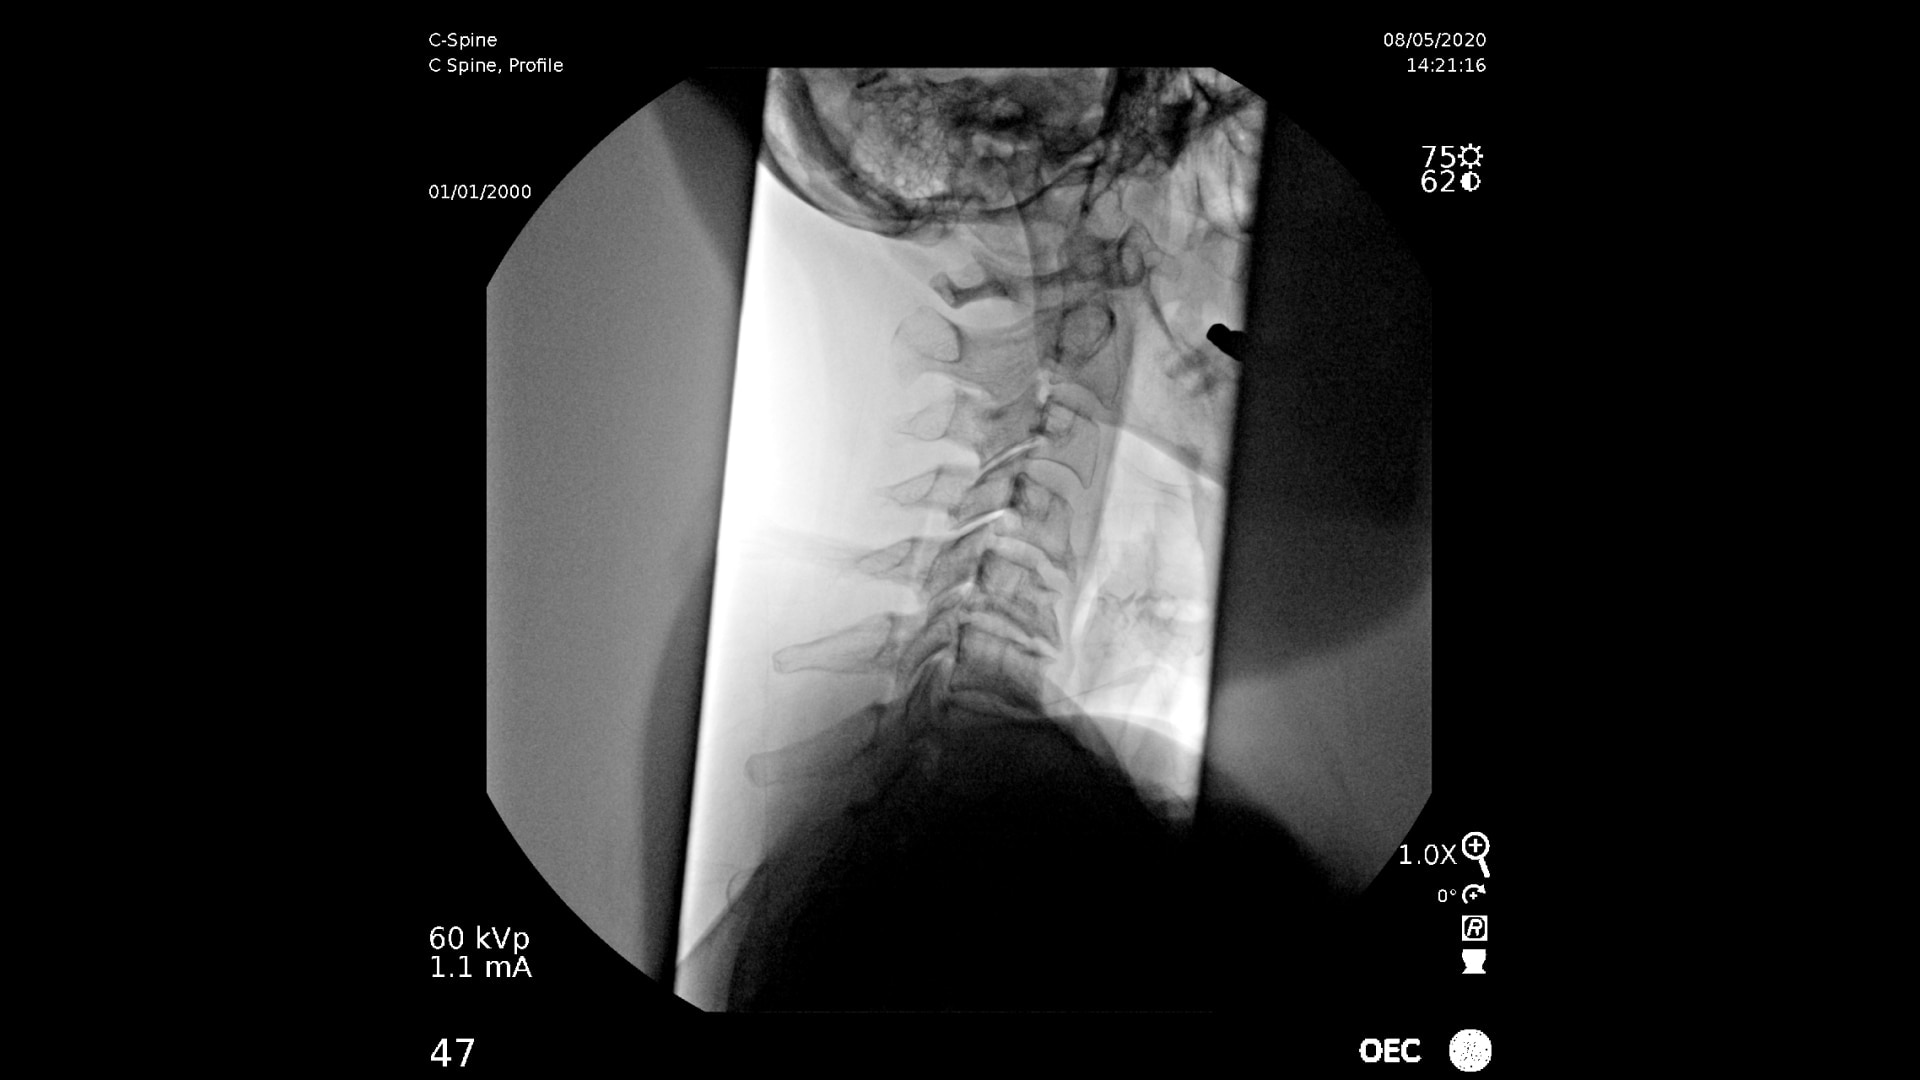

Consistently experience amazing image quality, precision, and efficiency during simple to complex pain management procedures with OEC C-arms.

Achieve precision and efficiency while experiencing the image quality needed during simple to complex pain management procedures with OEC C-arms.

OEC C-arms perform imaging in a variety of procedures such as:

• Cervical spine pain management